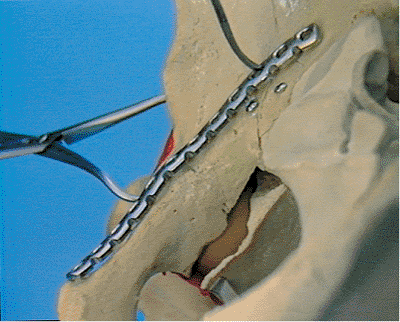

![]() |

Figure 42.20. A. Associated both-column fracture of the right acetabulum. View of the lateral aspect of the ilium. B.

Associated both-column fracture of the right acetabulum. Note the free triangular-fracture fragment at the iliac crest. There is also a free fracture fragment at the pelvic brim. (Reprinted with permission from AO/ASIF, Both Column Fracture Through the Ilioinguinal Approach [Video]. Copyright © AO/ASIF Video, 1991.

) |

Figure 42.21.

Farabeuf and Weber clamps are used in the reduction of the triangular iliac-crest fracture fragment. (Reprinted with permission from AO/ASIF, Both Column Fracture Through the Ilioinguinal Approach [Video]. Copyright © AO/ASIF Video, 1991.

Figure 42.22.

Screw is inserted between the tables of the ilium parallel to the iliac crest while the Weber clamp maintains the reduction. (Reprinted with permission from AO/ASIF, Both Column Fracture Through the Ilioinguinal Approach [Video]. Copyright © AO/ASIF Video, 1991.